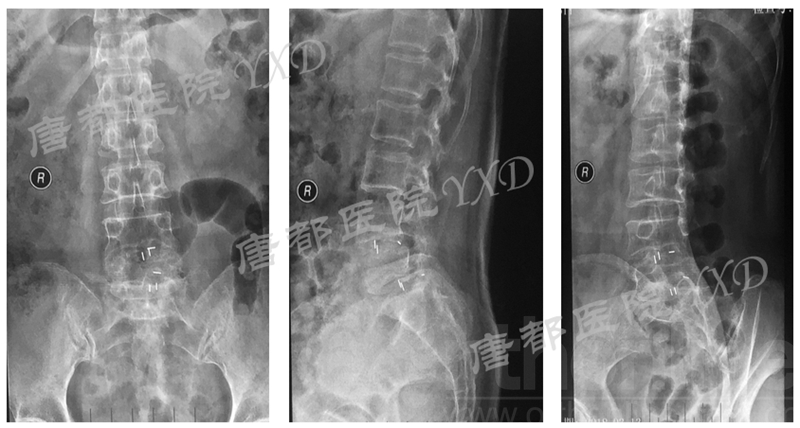

影像学检查:

诊断:腰椎间盘突出症术后复发

手术方案:显微镜辅助MI-TLIF腰椎翻修术